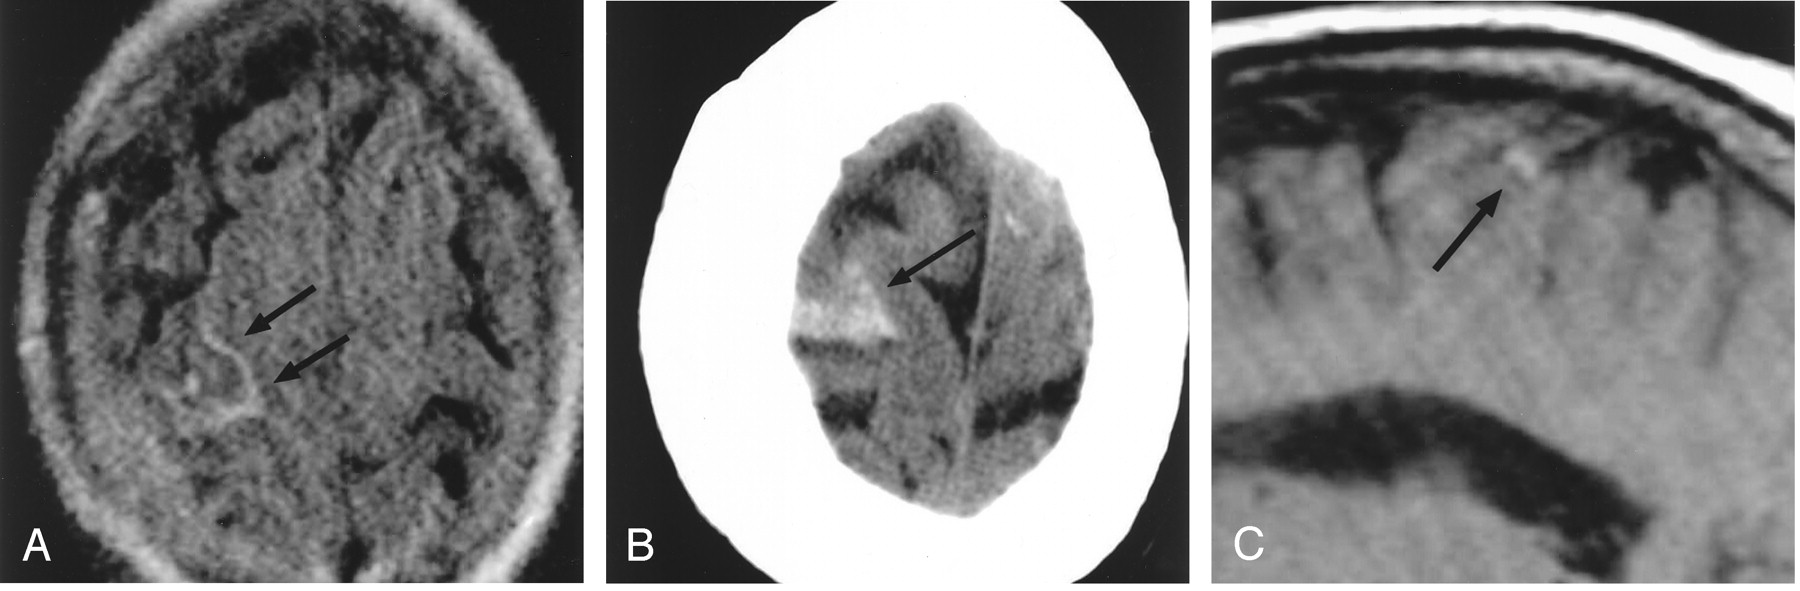

Patient 2, a 46-year-old woman with headaches and cortical venous thrombosis.

A, Axial FLAIR (10,327/158/2200) MR image shows focal sulcal hyperintensity (arrows), representing SAH in the right central sulcus. T2-weighted and diffusion-weighted images (not shown) were normal.

B, Right parasagittal T1-weighted (367/14) MR image shows luminal hyperintensity (large arrow), representing thrombus, in a right convexity cortical vein, probably the vein of Trolard. This abnormality was also identified on multiple adjacent sections. A flow void (small arrow) is seen in a more posterior, normal cortical vein.

C, Axial proton density–weighted (2267/30) MR image shows luminal hyperintensity (arrow) in a right convexity cortical vein; this was identified on multiple adjacent sections.

D, Right parasagittal T1-weighted (367/14) MR image, obtained approximately 3 months after the image in panel B, shows restoration of the normal signal intensity void (large arrow), representing recanalization in the previously occluded cortical vein. The more posterior cortical vein (small arrow) is unchanged.

E, Axial proton density–weighted (2450/30) MR image, obtained approximated 3 months after the image in panel C, shows a small signal intensity void (arrow) in the previously thrombosed cortical vein.

The patient was admitted to the hospital by the neurology service and placed on heparin and warfarin anticoagulation. She developed intermittent jerking of her left arm and was placed on antiepileptic medication for empiric treatment of simple partial seizures. Findings at a comprehensive hypercoagulability workup were normal. The patient improved and continued to take warfarin as an outpatient.

Follow-up MR imaging was obtained approximately 3 months after the patient’s initial presentation. This showed resolution of the tubular structure of high signal intensity previously seen on the T1- and proton density–weighted images (Fig 2D and E).